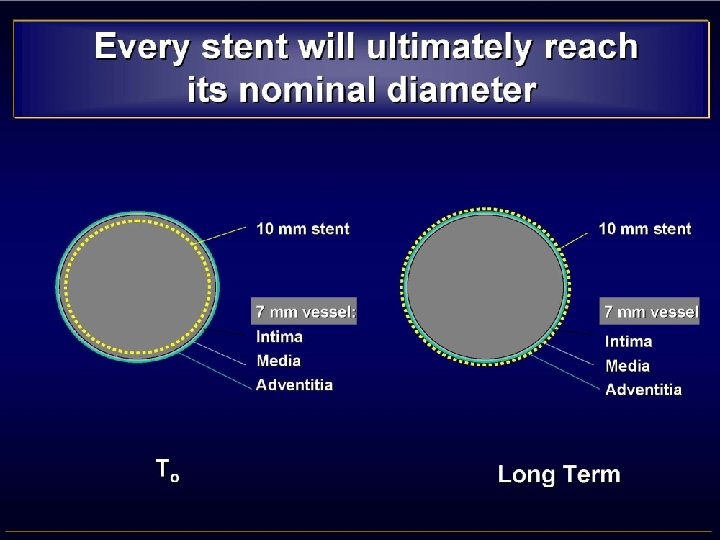

• MISMATCH CCA-ICA